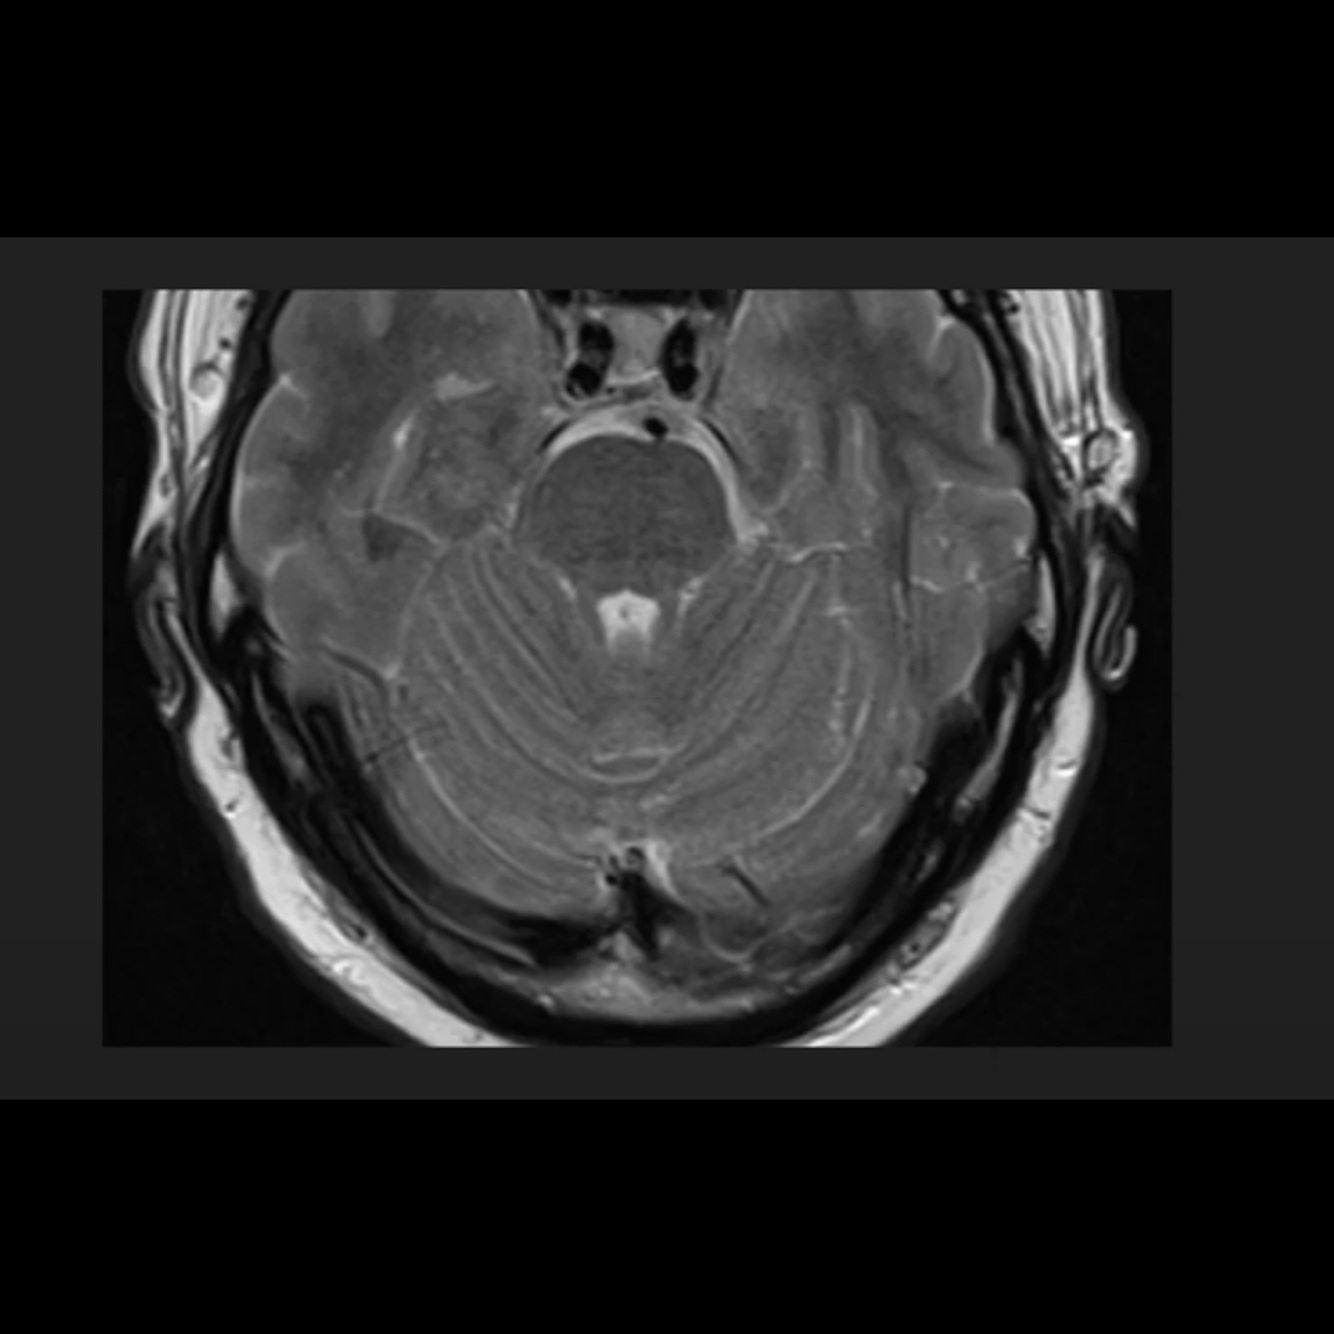

Which structure is filled with CSF and surrounds the brainstem and what is it called, and which structure is the fourth ventricle?

A

) basal cistern